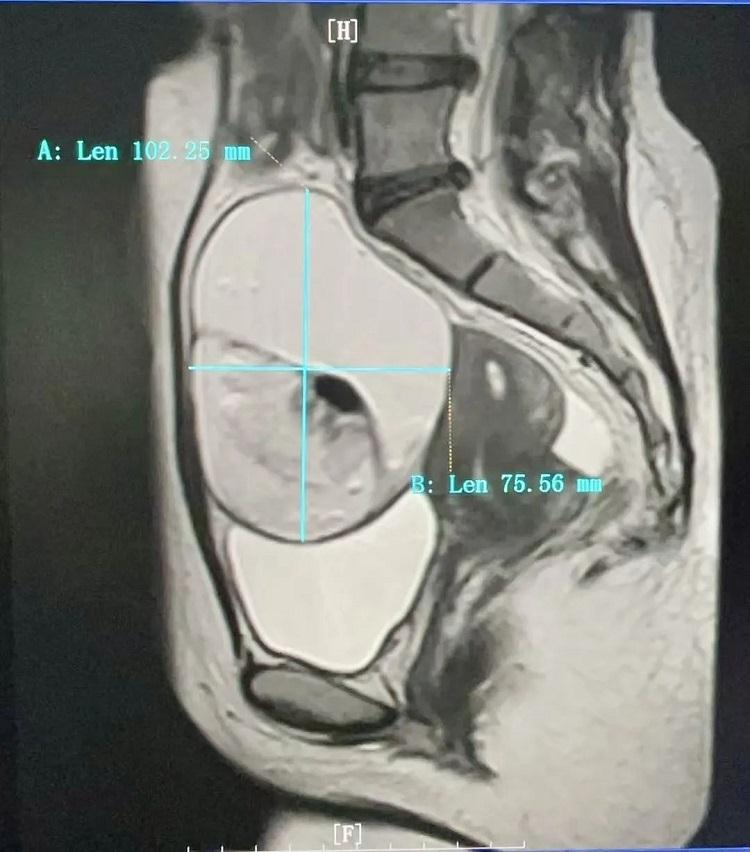

在山东济南工作的小熙因持续下腹部不适,在山东当地医院初诊考虑妇科疾患,多方打听到新近调任国产自拍av 的副院长刘达宾主任医师、副教授擅长妇科疾病诊治,慕名从山东奔赴三千里前来国产自拍av 求诊。刘达宾主任医师接诊后迅速对小熙进行了专业详细的问诊、体检及相关影像学检查。一查妇科彩超及盆腔MRI,结果让小熙及亲人均大吃一惊,姑娘瘦弱的身体里居然藏着一个直径约11cm左右的巨大肿物,子宫后方的巨大囊实性肿物几乎占据了整个盆腔,手术难度极大!

盆腔核磁检查影像考虑到小熙的年龄和生育意愿,还有小熙对手术后留疤以及对生育功能潜在影响的担忧,刘达宾主任医师组织团队开展术前讨论,决定采用更为先进、微创的手术方式进行治疗。在刘达宾主任医师的带领下,手术团队凭借精湛的技术和默契的配合,成功实施单孔腹腔镜卵巢肿瘤剥除手术。该术式不仅最大限度保护了患者的生育功能,同时也兼顾美观,达到双赢效果。“